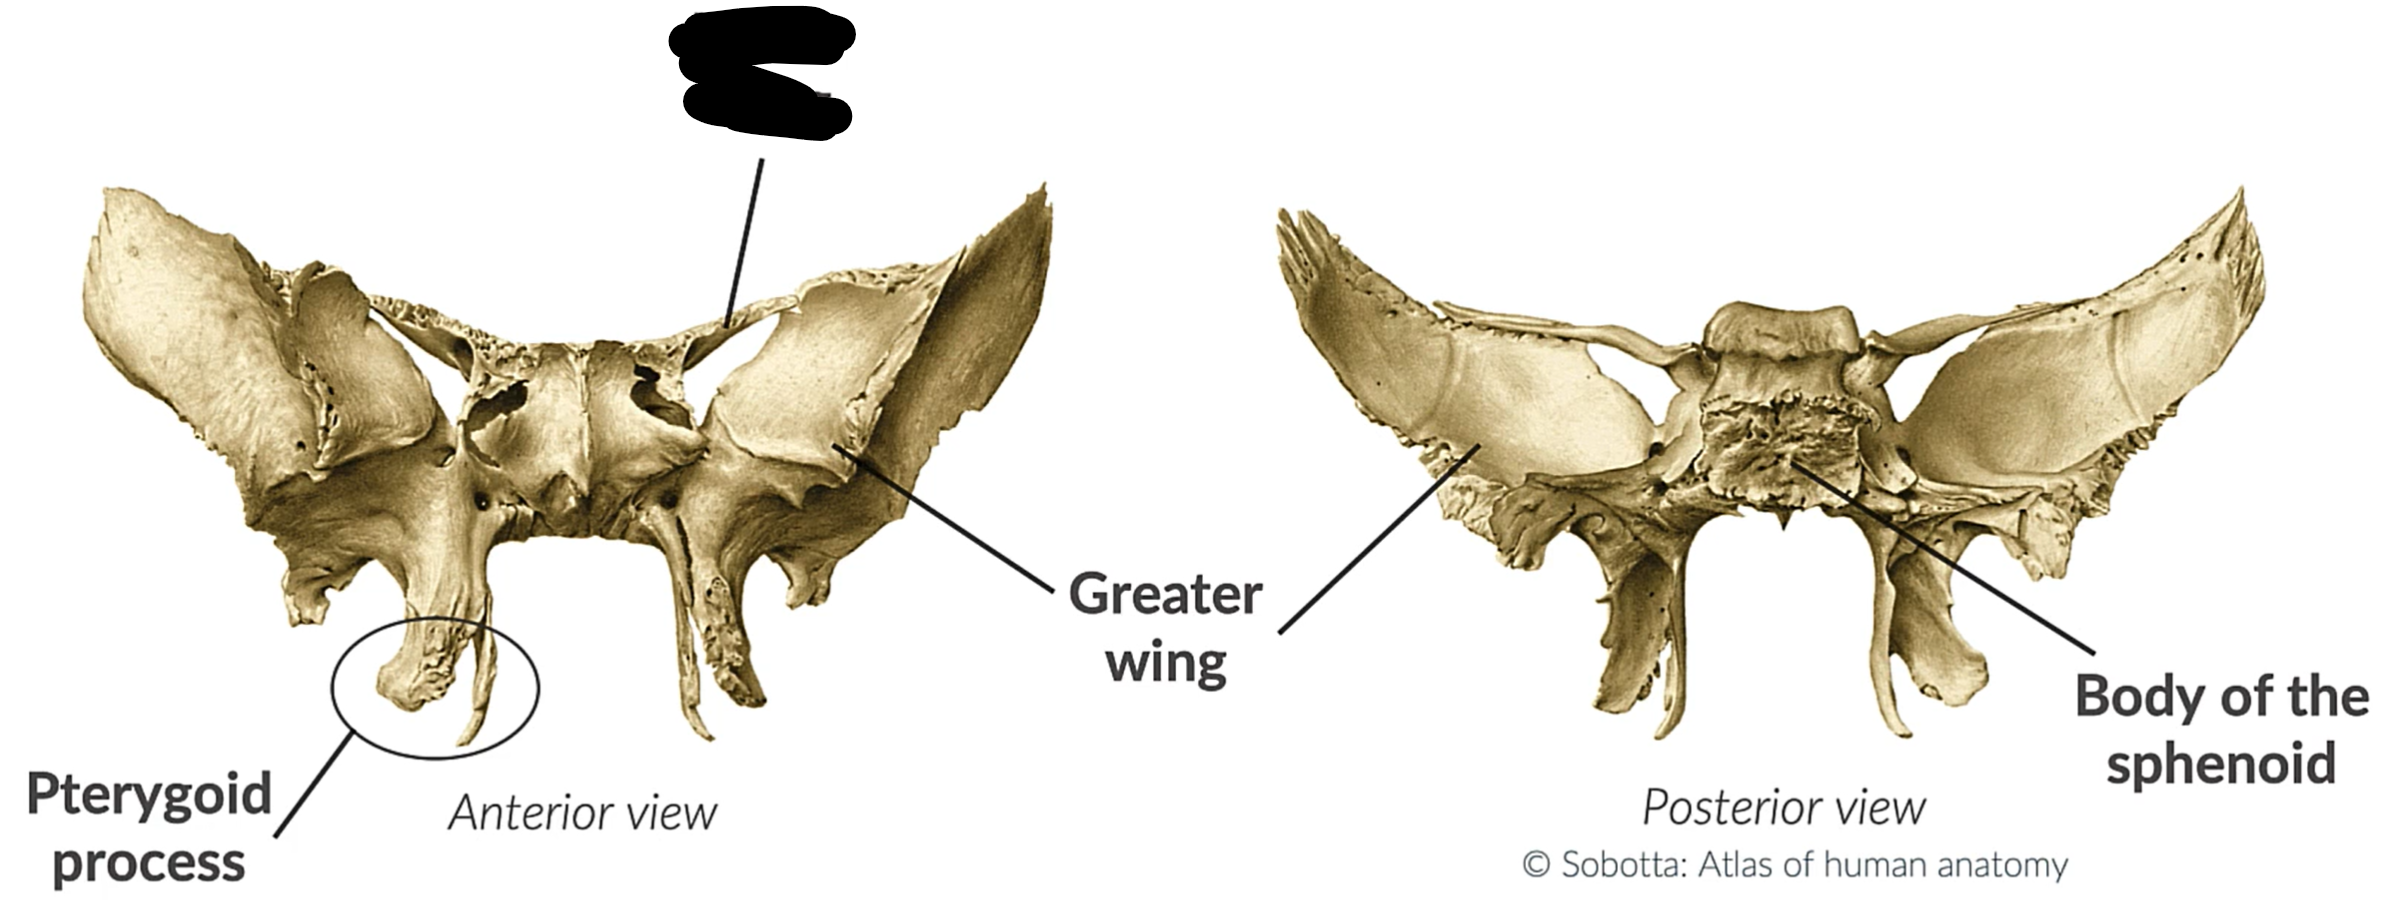

What bone is this?

Sphenoid bone

Lesser wing

Greater wing

Pterygoid process

Body sphenoid bone